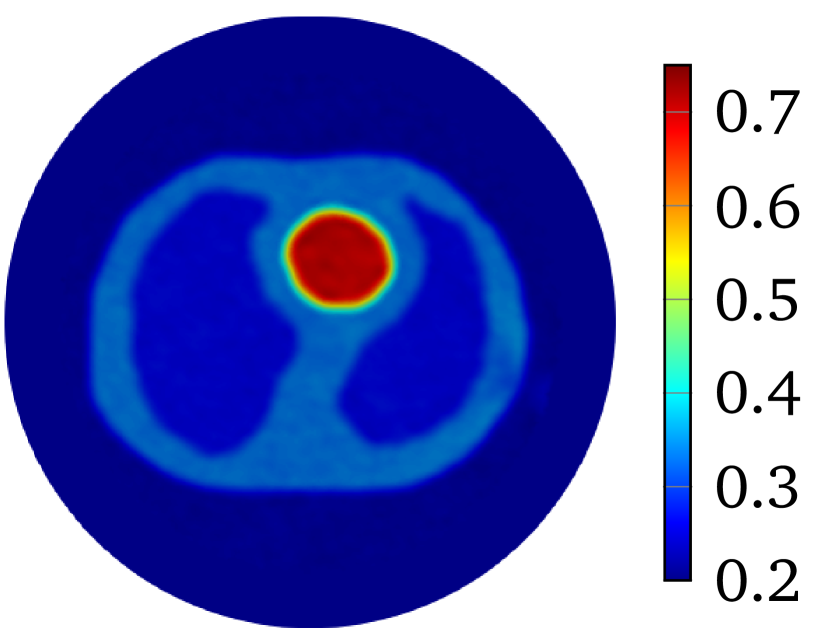

The first example is a heart-lung model [35], see Figure 1(a). The considered three tissues are heart (red, ), lung (cyan, ), and soft-tissues (blue, ). The model is placed into a circular region with a background material (white, ) and a radius .

to produce with for 2D problem. The constant is selected so that . The value of is and for heart-lung model and human-brain model, respectively. The true smoothed distributions of for the two models are shown in Figure 2.